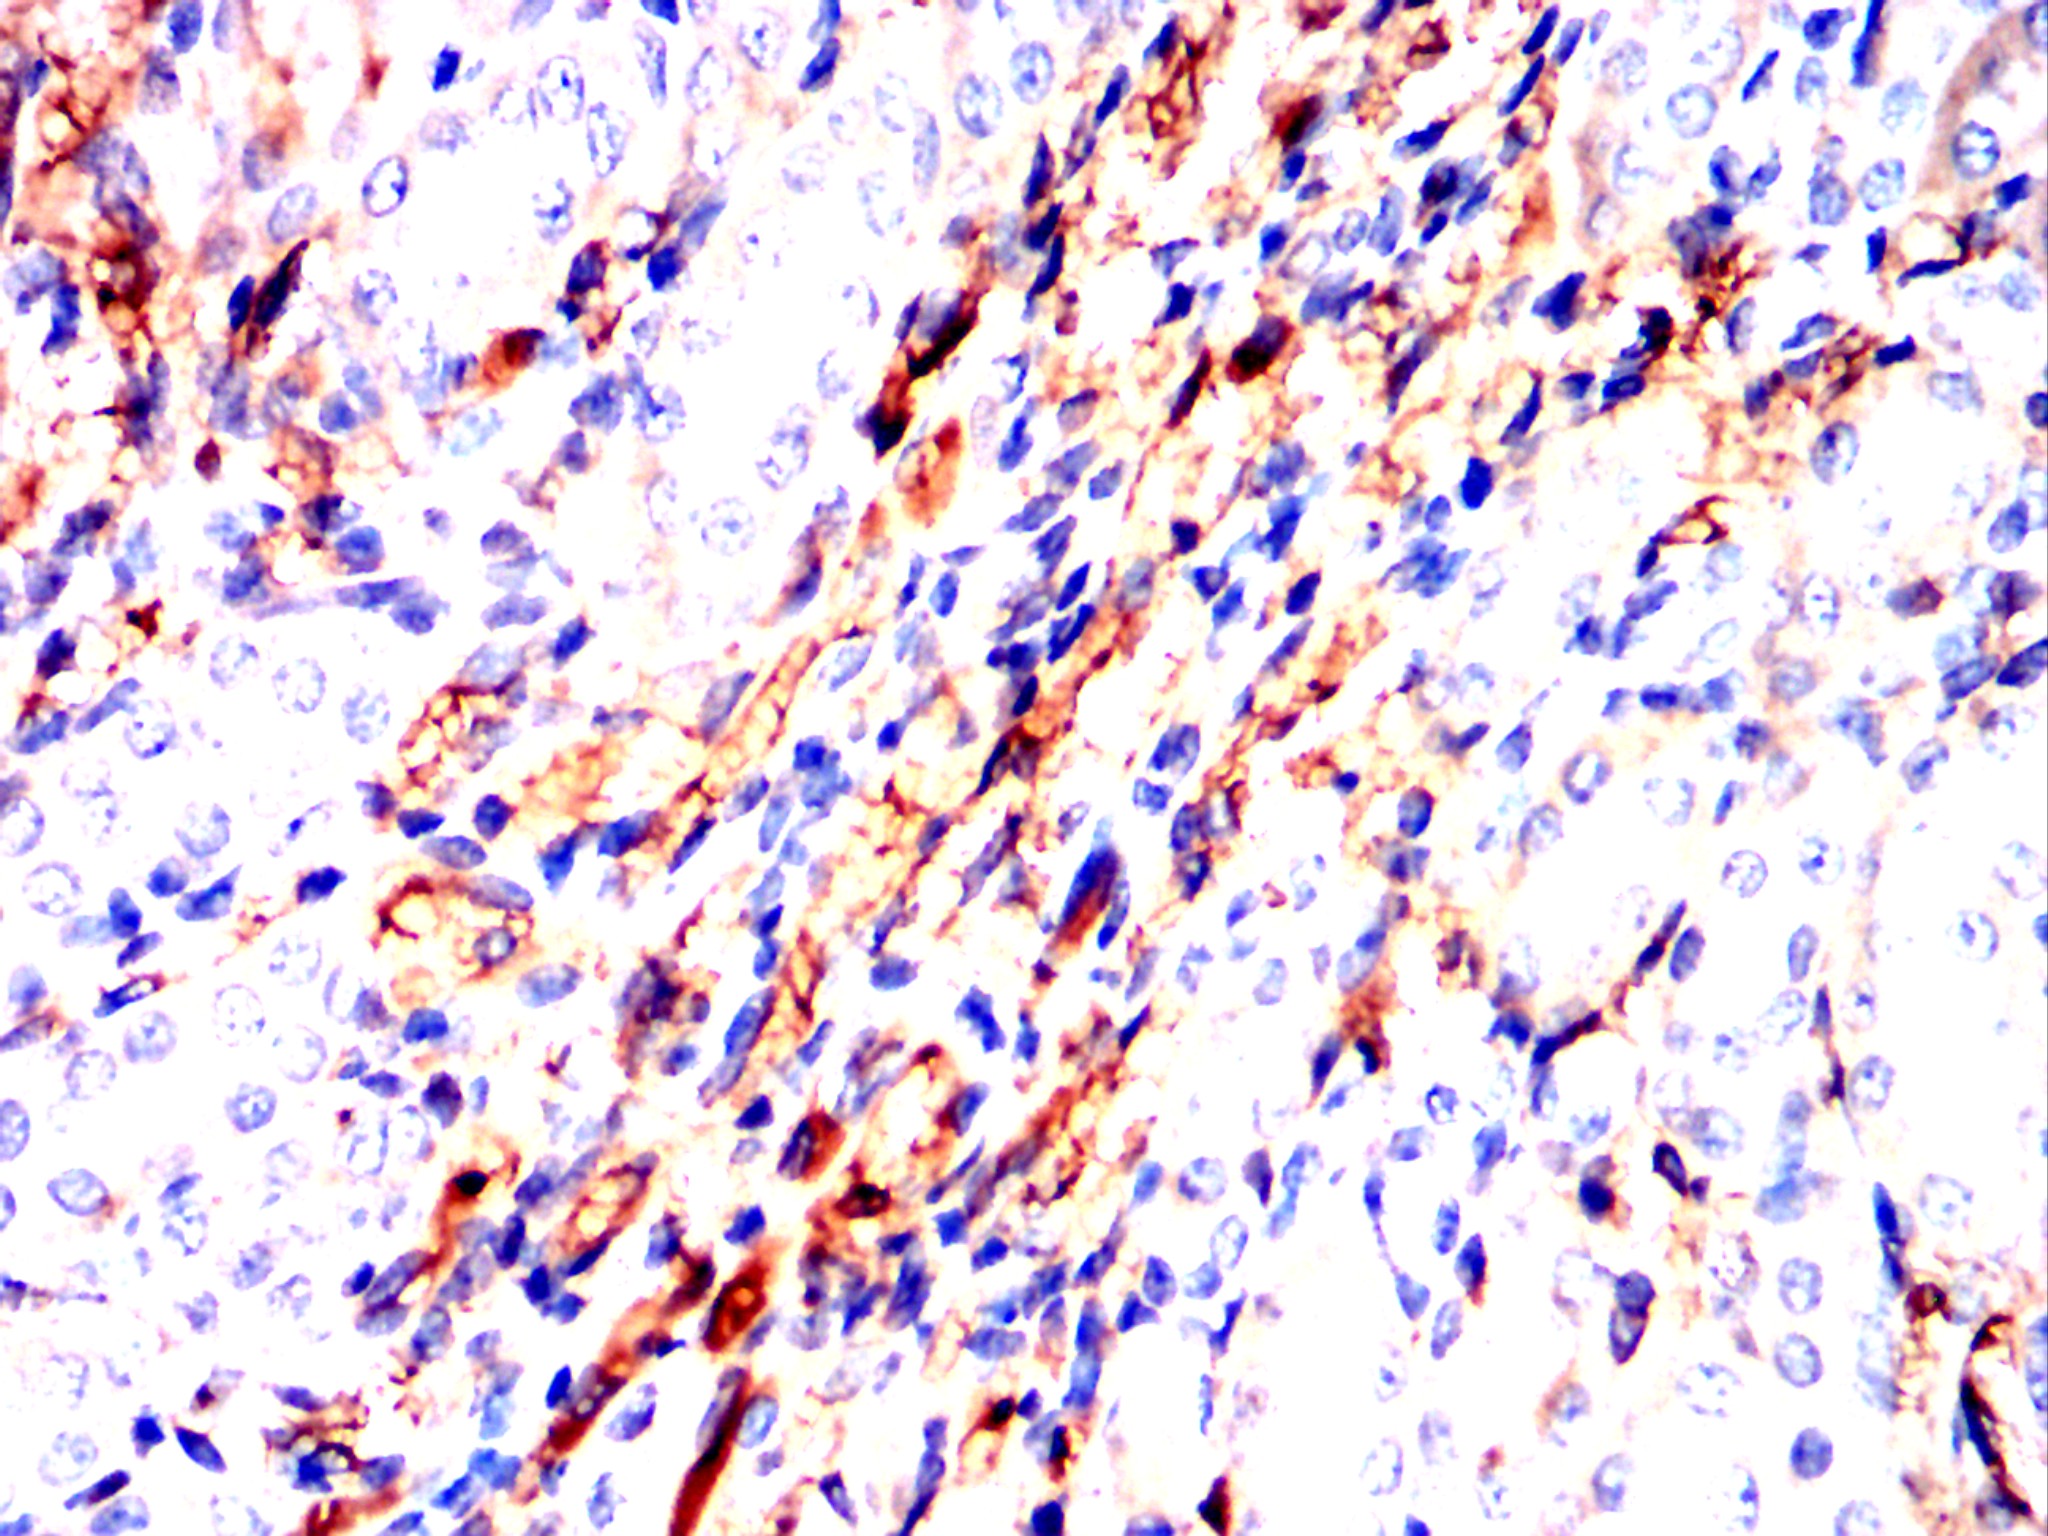

Immunohistochemical analysis of paraffin-embedded human endometrial cancer tissues using NT5E mouse mAb with DAB staining.